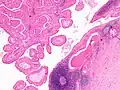

This Warthin's tumor presented as a parotid mass in a middle-aged male, who underwent superficial parotidectomy. The tumor, at the right of the image, is well-demarcated from the adjacent parotid tissue and tends to shell out from it.

Low magnification micrograph of a Warthin tumor arising from the parotid gland.

Histopathology of Warthin tumor in the parotid gland. H&E stain.